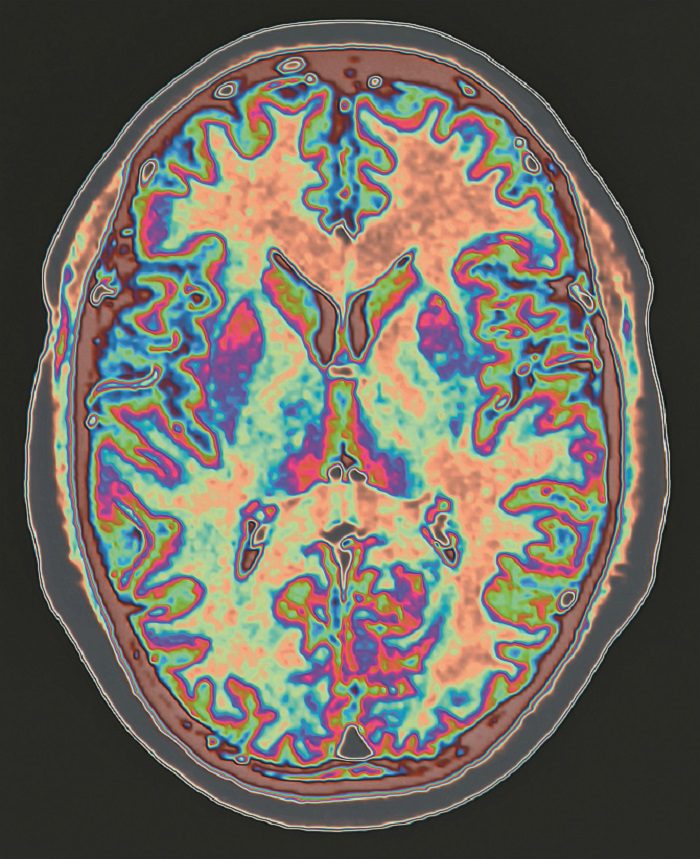

COVID-19 may change the brain, we heard from Gwenaëlle Douaud, PhD. A study comparing brain scans from people before and after SARS-CoV-2 infection suggests that even minor cases of COVID-19 may cause a loss of gray matter in the orbitofrontal cortex and parahippocampal gyrus (the regions of the brain associated with smell). Study participants who had COVID-19 also showed a greater cognitive decline between their two scans than people in a control group. The decline was associated with the atrophy of a specific part of the cerebellum linked to cognition.